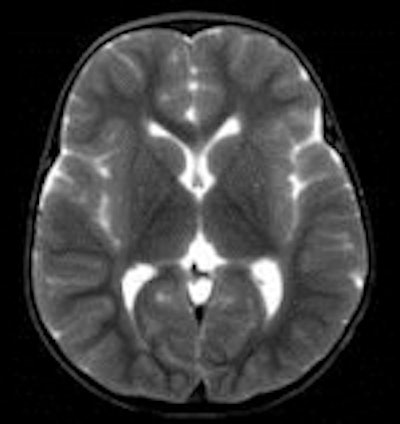

A team of radiologists from Churchill Hospital in Oxford and the Manchester Royal Infirmary determined that CT scans were more accurate than MRI examinations for providing a cause of death compared with traditional autopsy. Additionally, they estimated that post-mortem imaging could eliminate the need for autopsy in up to half of all cases. But regrettably, it fell short in determining common causes of sudden death, proving not to be as reliable a diagnostic tool as had been hoped.

CT and MRI exams were performed during evening and night shifts at times when scanners were not in use for the hospitals' patients. The bodies, contained in sealed body bags, were imaged in the supine position. Two radiologists first independently interpreted the exams, preparing individual reports. They subsequently prepared a consensus report. Additionally, brain scans were reported by a specialist neuroradiologist, and a specialist cardiac radiologist also interpreted findings and prepared a report. All radiologists limited their reports to noting only findings that could pertain to cause of death.

Based on their findings, the radiologists determined that an autopsy could have been avoided for 34% of the cases based on CT exam reports, 42% based on MRI reports, and 48% based on consensus reports. In many cases, imaging proved to be better than autopsy in detecting pneumothorax, intracranial pathologies, and some fractures, the authors wrote.